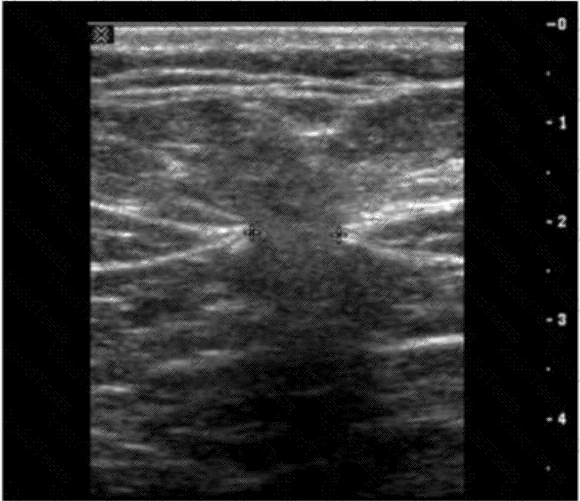

The ultrasound image demonstrates a classic example of ascites, shown by the anechoic (dark) fluid located between bowel loops or surrounding abdominal organs. In this case, there appears to be a small fluid collection in the peritoneal cavity.

One of the key maneuvers used to differentiate free fluid (such as ascites) from loculated fluid or other structures is to reposition the patient. Asking the patient to “turn from side to side” (Option D) can help in assessing whether the fluid shifts position — a hallmark feature of free intraperitoneal fluid. This positional change is highly useful in confirming the diagnosis and distinguishing ascites from other potential mimics (e.g., cystic masses, lymphoceles, or bowel wall thickening).